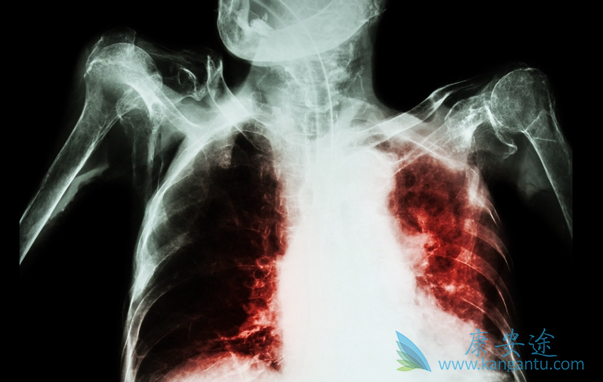

肺癌中晚期能治好吗?治疗肺癌方法有哪些?

肺癌,是目前全人类的杀手。在我国肺癌是发病率和死亡率双高的恶性肿瘤。从19世纪起,人类陆续开始尝试用手术、放射、化疗等方式来治疗肺癌,但是效果并不理想。大量临床数据表明,肺癌早期的5年生存率高达70%~80%以上,而晚期肺癌的5年生存率为5%以下。随着科学与技术的不断发展,时下,靶向药物、免疫疗法成为新一代的治疗手段深受追捧。那现在肺癌中晚期能治好吗

对于中晚期肺癌,传统的治疗方法多是化疗联合局部放疗,平均生存期只有1年左右,这也是谈肺癌色变的主要原因。近年来,随着肿瘤分子遗传学的发展,针对肺癌驱动基因和表观遗传学的深入研究,肺癌的靶向治疗、免疫治疗等如火如荼地开展起来了,通过这样的“精准”治疗,中晚期肺癌的5年生存率得到大大提高,肺癌成为“慢性病”的时代即将到来,肺癌的治疗永远在路上,中晚期肺癌并非不可治。